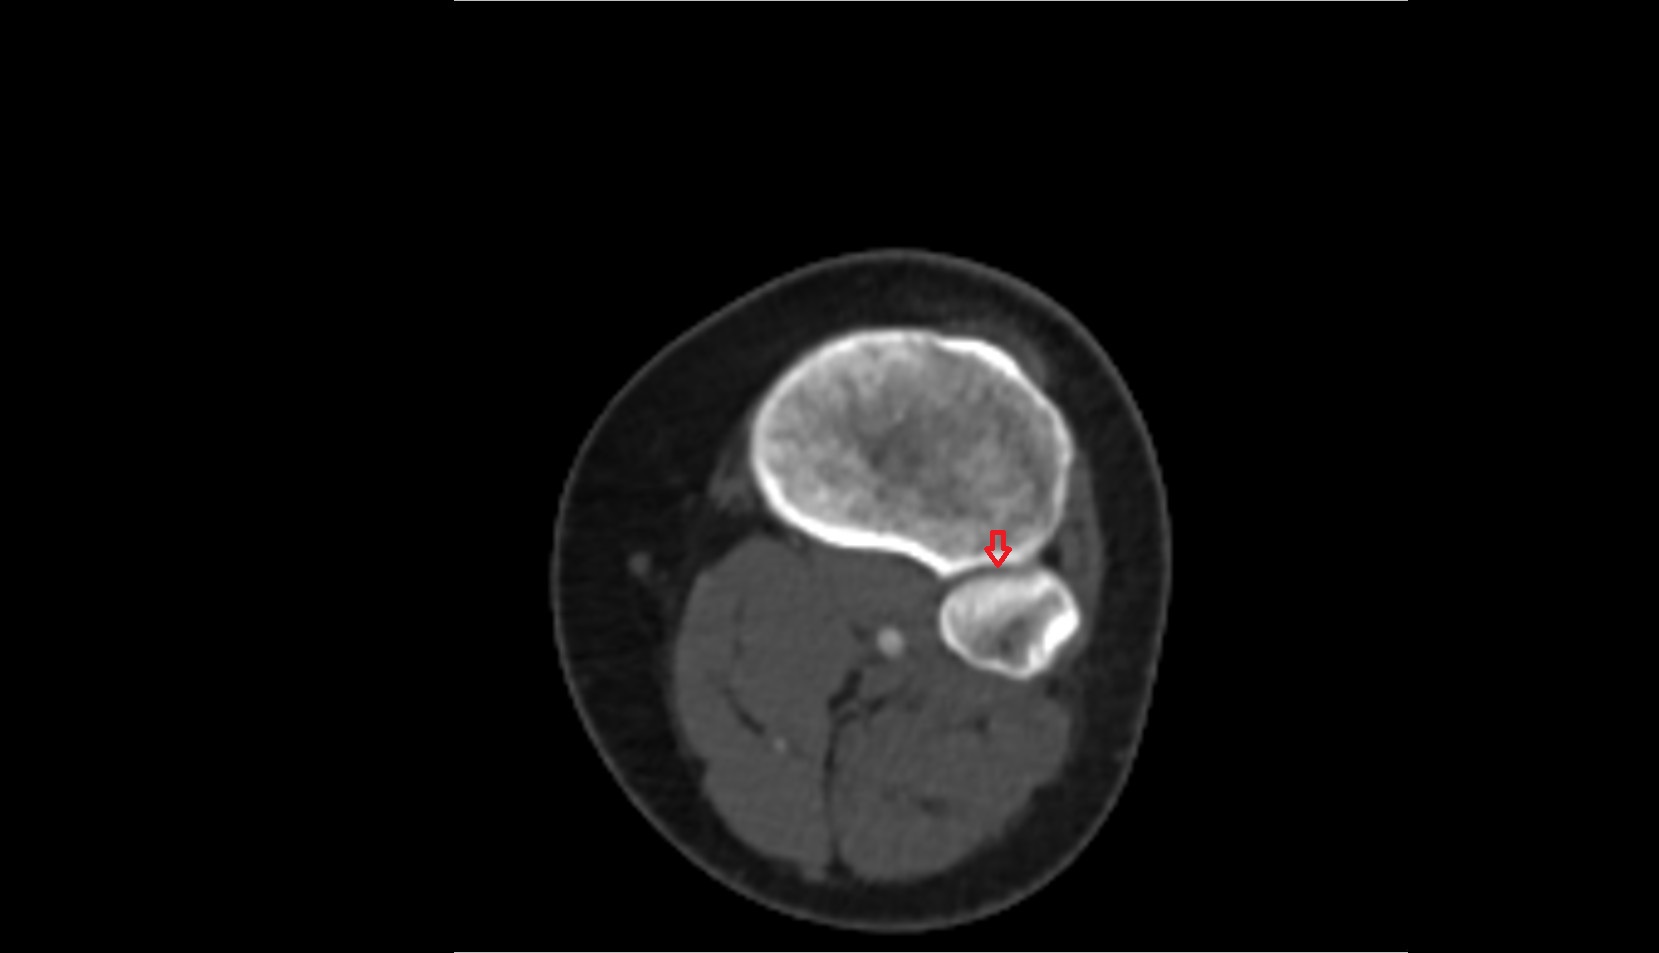

- Knee Joint